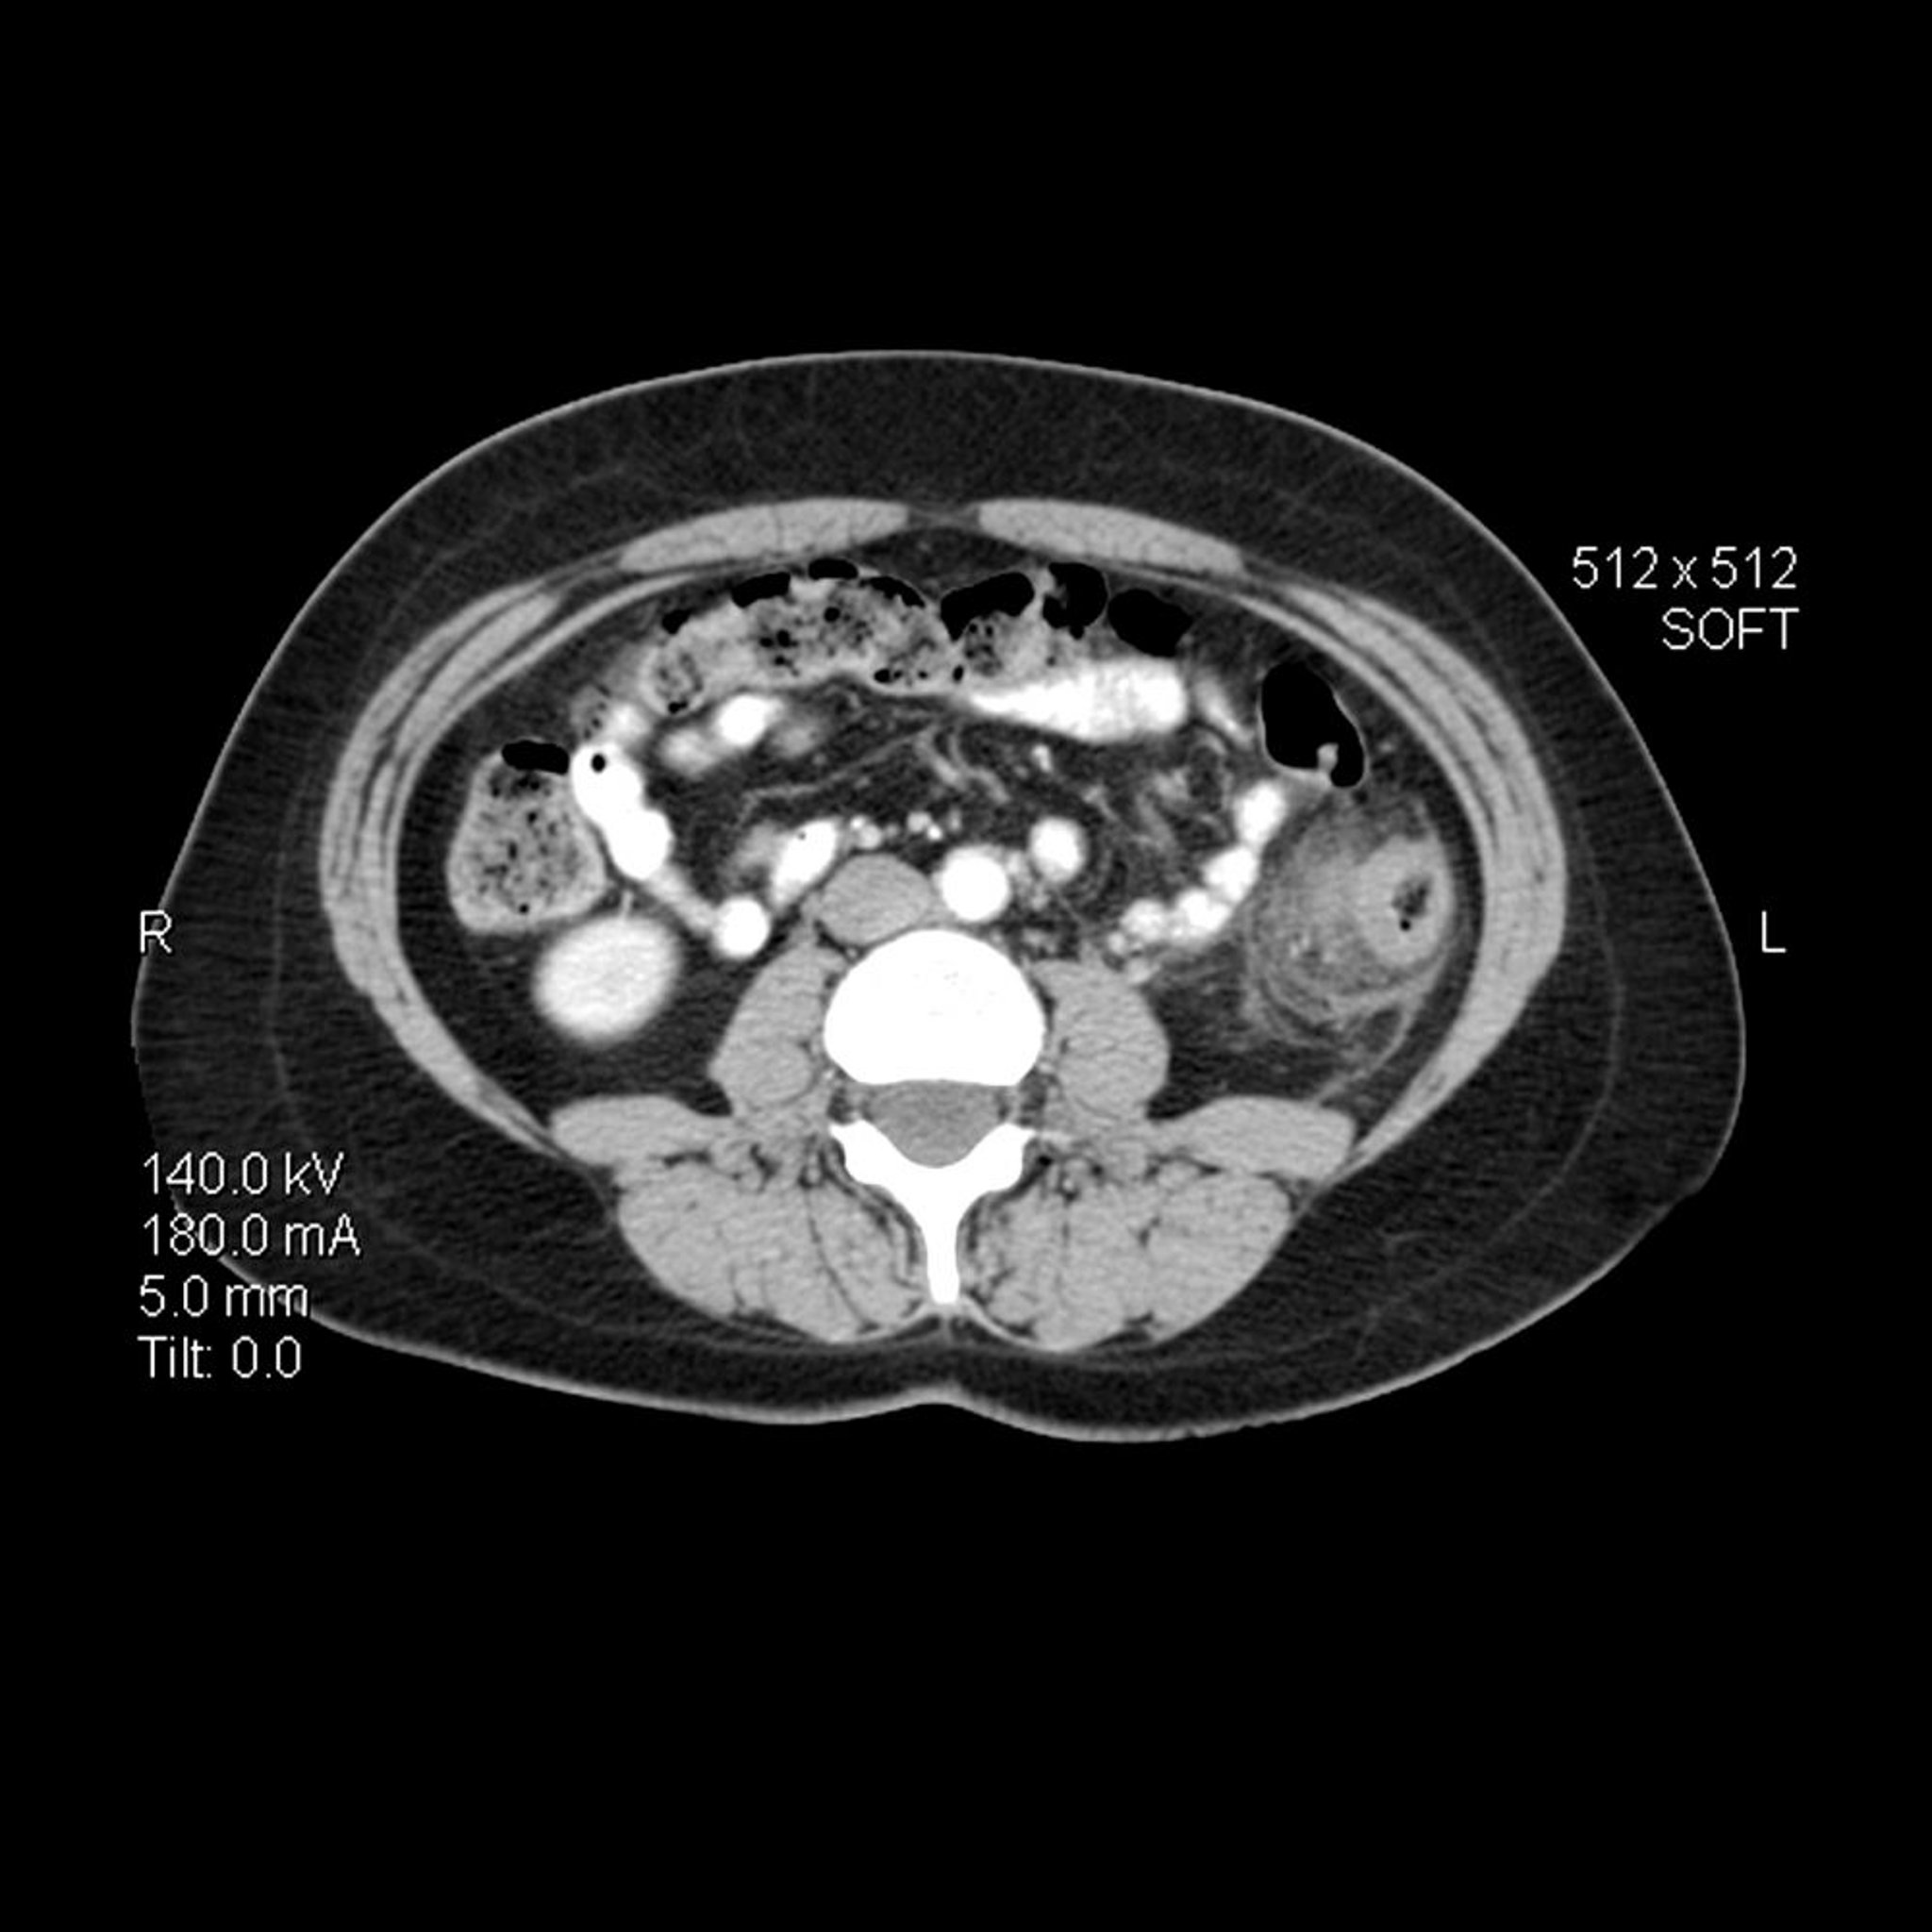

Дивертикулит (КТ-сканирование)

На этом осевом (поперечном) КТ- снимке живота у человека с дивертикулитом утолщена стенка нисходящей ободочной кишки. В окружающем кишечник висцеральном жире также имеются воспалительные прожилки с повышенной плотностью.